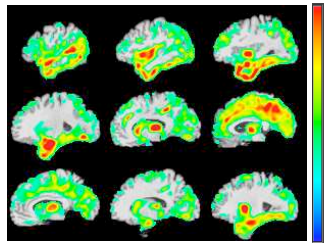

I am an Assistant Professor at the Department of Electrical and Computer Engineering at Boston University. My research is at the intersection of medical vision (medical image analysis), machine learning, and bioinformatics. I develop algorithms to analyze and understand medical images, genetic data, and other electrical health records, such as clinical reports. The main themes of research in my lab are about the main challenges of AI in healthcare: (1) Explainability, (2) Data Efficiency, (3) Multimodal Data Fusion, and Causality. My lab works on Alzheimer’s Disease, Chronic Obstructive Pulmonary Disease (COPD), and Non-Alcoholic Fatty Liver Disease (NAFLD) projects. Our research is supported by funding from NIH, NSF, and industry awards. Read More